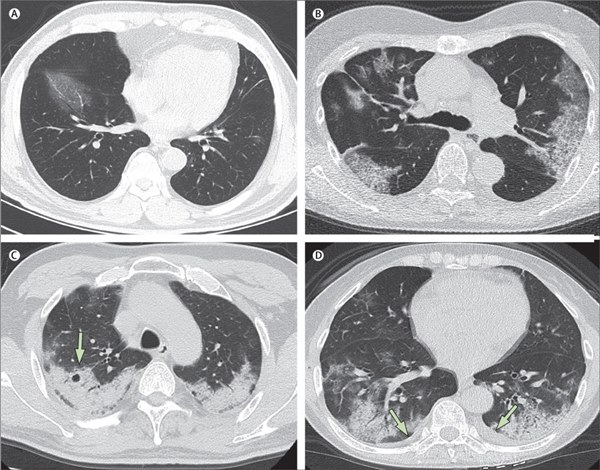

Hình CT chụp phổi của các bệnh nhân Covid-19 tại Trung Quốc.Hình A: Bệnh nhân nam 56 tuổi, ngày thứ 3 sau khi khởi phát triệu chứng, phổi xuất hiện các đốm trắng từ vách liên sườn đến nội nhãn ở thùy dưới bên phải. Hình B: Bệnh nhân nữ 74 tuổi, ngày thứ 10 sau khi khởi phát triệu chứng: hai bên phổi dày đặc những đốm trắng chứng tỏ sự xâm chiếm và phá hủy nặng của virus corona tới các phế nang. Hình C: Nữ bệnh nhân 61 tuổi, ngày 20 sau khi khởi phát triệu chứng: phổi bị bao phủ bởi lớp trắng mờ đục dày, các phế nang bên trong đã bắt đầu biến đổi. Hình D: Nữ bệnh nhân 63 tuổi, ngày 17 sau khi khởi phát triệu chứng: hai bên phổi xuất hiện lớp đốm trắng dày trong phế quản ở cả thùy dưới lẫn thùy trên, đã có hiện tượng tràn dịch màng phổi. Ảnh: The Lancet.